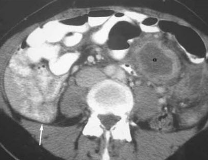

Bowel Malrotation

<div id="article-content-body"> <p><img alt="" src="/sites/default/files/images/ConPCAppenA.jpg" style="height:119px; margin-left:8px; margin-right:8px;...